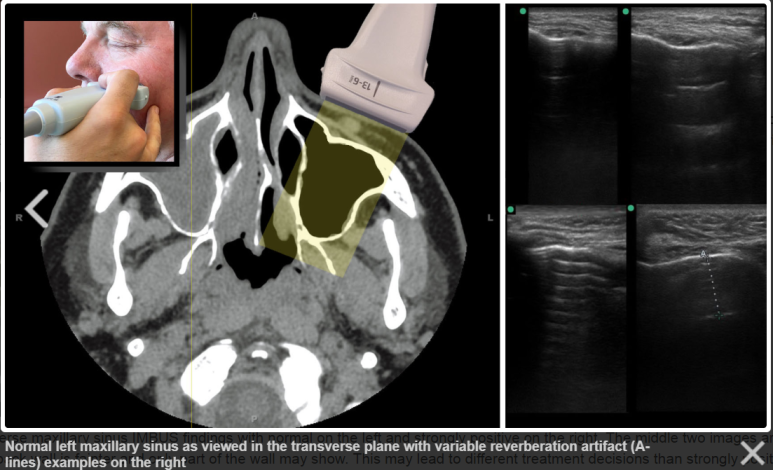

정상 부비동의 이미지 http://imbus.anwresidency.com/txtbook/02_sinus.html

정상 부비동은

폐(Lung)처럼

공기로 가득 차있어서

Air Artifact만 나타납니다.

공기의 공명으로 인해

초음파 빔이 투과하지 못하고

흩어져버립니다.

때문에

부비동 벽의 경계가

보이지 않습니다.